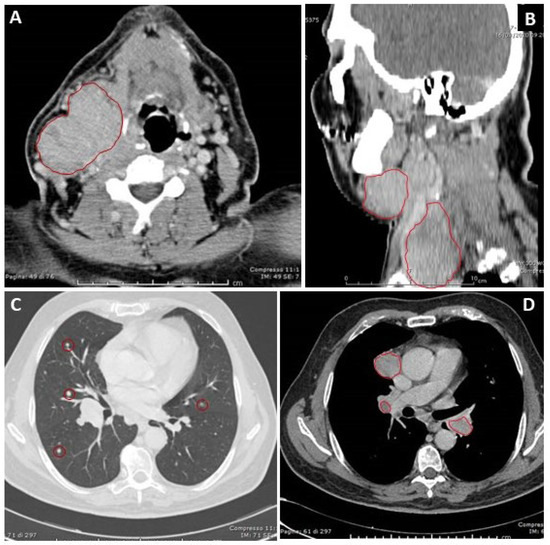

3.1. Case Report

3.1.1. Clinical Presentation and Initial Treatments

3.1.2. Progression of Disease and Subsequent Treatments